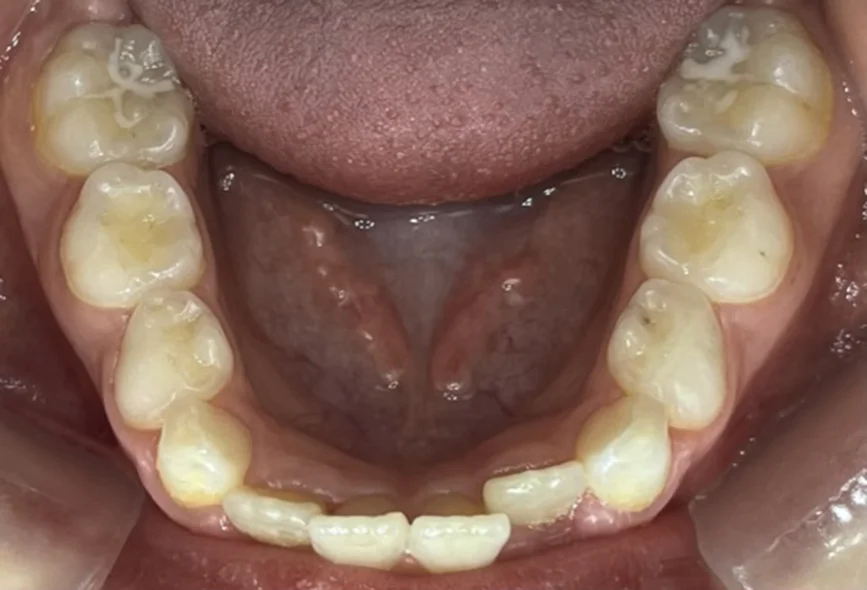

След една година започва лечението с алайнери. Следва интраорален скенер, анализ на рентгенографии, изработка на алайнери, поставяне на атачмънти , контролни прегледи и накрая сваляне на атачмънти.

Клинични резултати:

Хармонични зъби дъги с достатъчно място за пробива на постоянните зъби.

Осигуряване на възможност за правилен растеж и съотношение на двете челюсти.